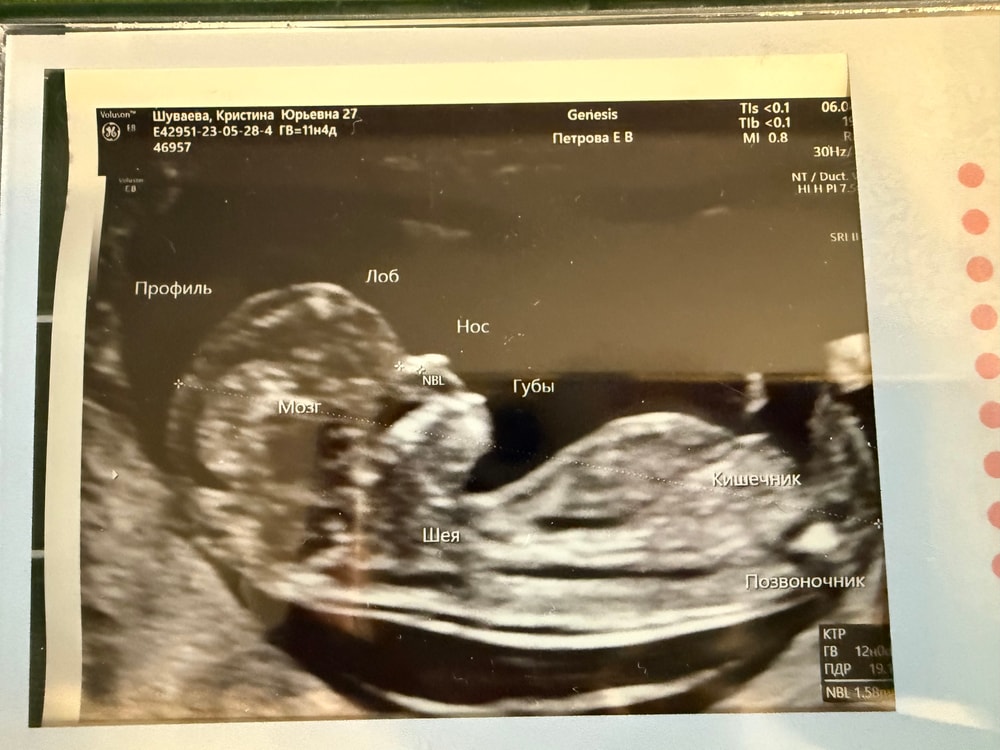

Пол малышаСегодня была на узи скрининге. По месячным срок 11+4, по ктр 12 недель ровно. Предположили вторую дочку по половому бугорку.

Кристина, чудесный малышок! Но бугорка не видно( в так бы посмотрела и подумала, что девочка